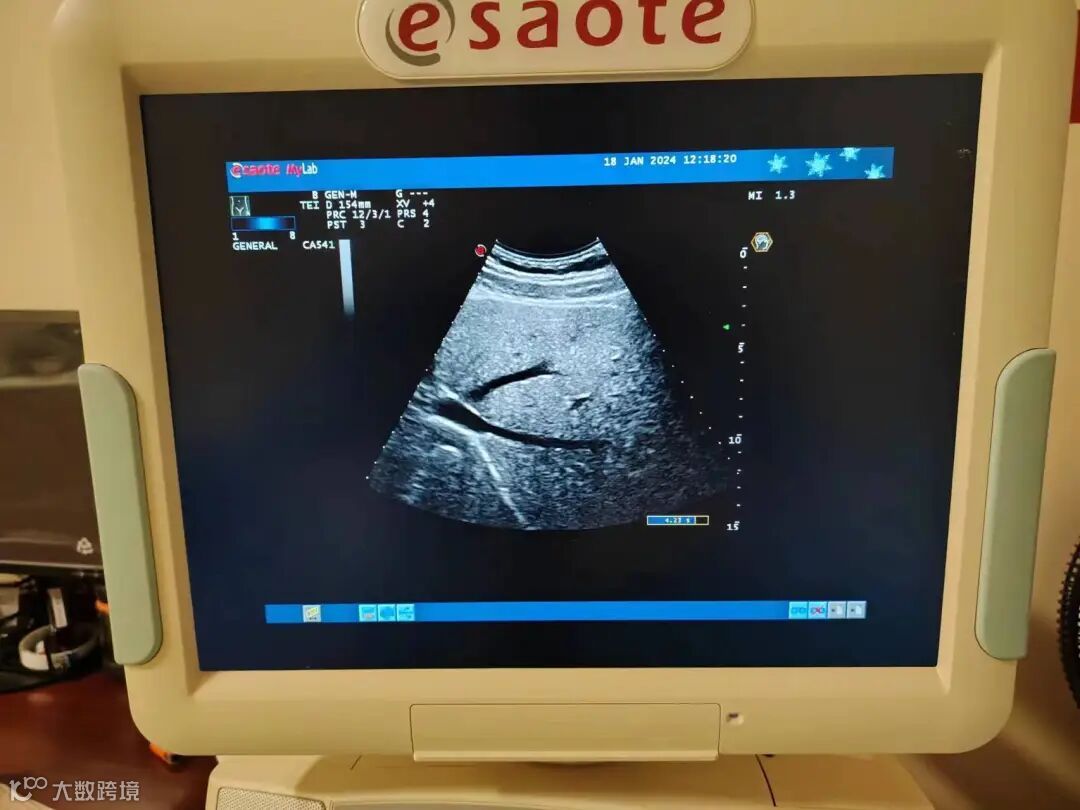

1.故障现象

图像大面积缺失。

3.故障判定与分析

长期使用导致声头阵元大面积衰减和缺失,透镜破裂,图像缺波严重。